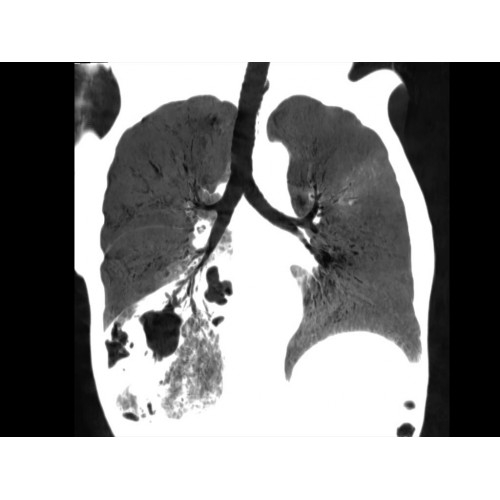

Позволяет проводить комплексные исследования всех анатомических зон, включая нейровизуализацию, ангиографию, исследования органов грудной и брюшной полости. Особенно эффективен для раннего выявления онкологических заболеваний.